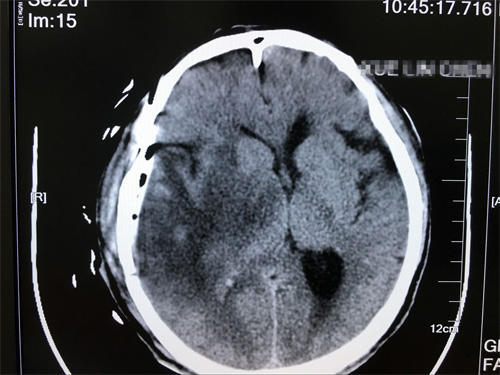

术后影像:未见肿瘤残余,未见异常明显病灶

手术后第3天,陈老汉平安转到普通病房,术后第5天,引流管顺利拔除,在家人的照顾下,恢复越来越好。薛老汉的女儿说:“真的非常感谢沈教授,以很快的速度帮我们解除了痛苦,现在父亲终于不要再受脑瘤折磨了。看着他身体一点点好转,我们做子女的遗憾也少一点”。除了感谢沈教授,薛老汉的女儿还对医院的服务赞不绝口,她说:“父亲在这里住院,一个病房的患者和家属相处都非常融洽,医生每天查房,很有耐心,护士姑娘们也非常温柔,脾气很好。马上就要出院了,真的十分感谢各位病友和医护人员的照顾”。